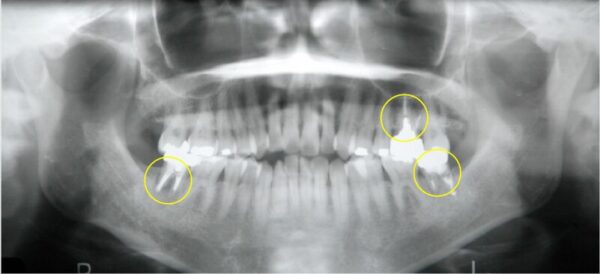

黄色で〇をつけた歯は、すでに神経の無い「失活歯」です。

通常、抜歯が必要な矯正治療では真ん中あたりの4,5番目の歯を抜くことが多いです。

そうすることで奥歯と前歯の間にスペースが出来るため、綺麗に並べやすいからです。

しかしこの方は4,5番目の歯は健康で神経のある「生活歯」であったため、何とかこれを残せないものかと考えました。